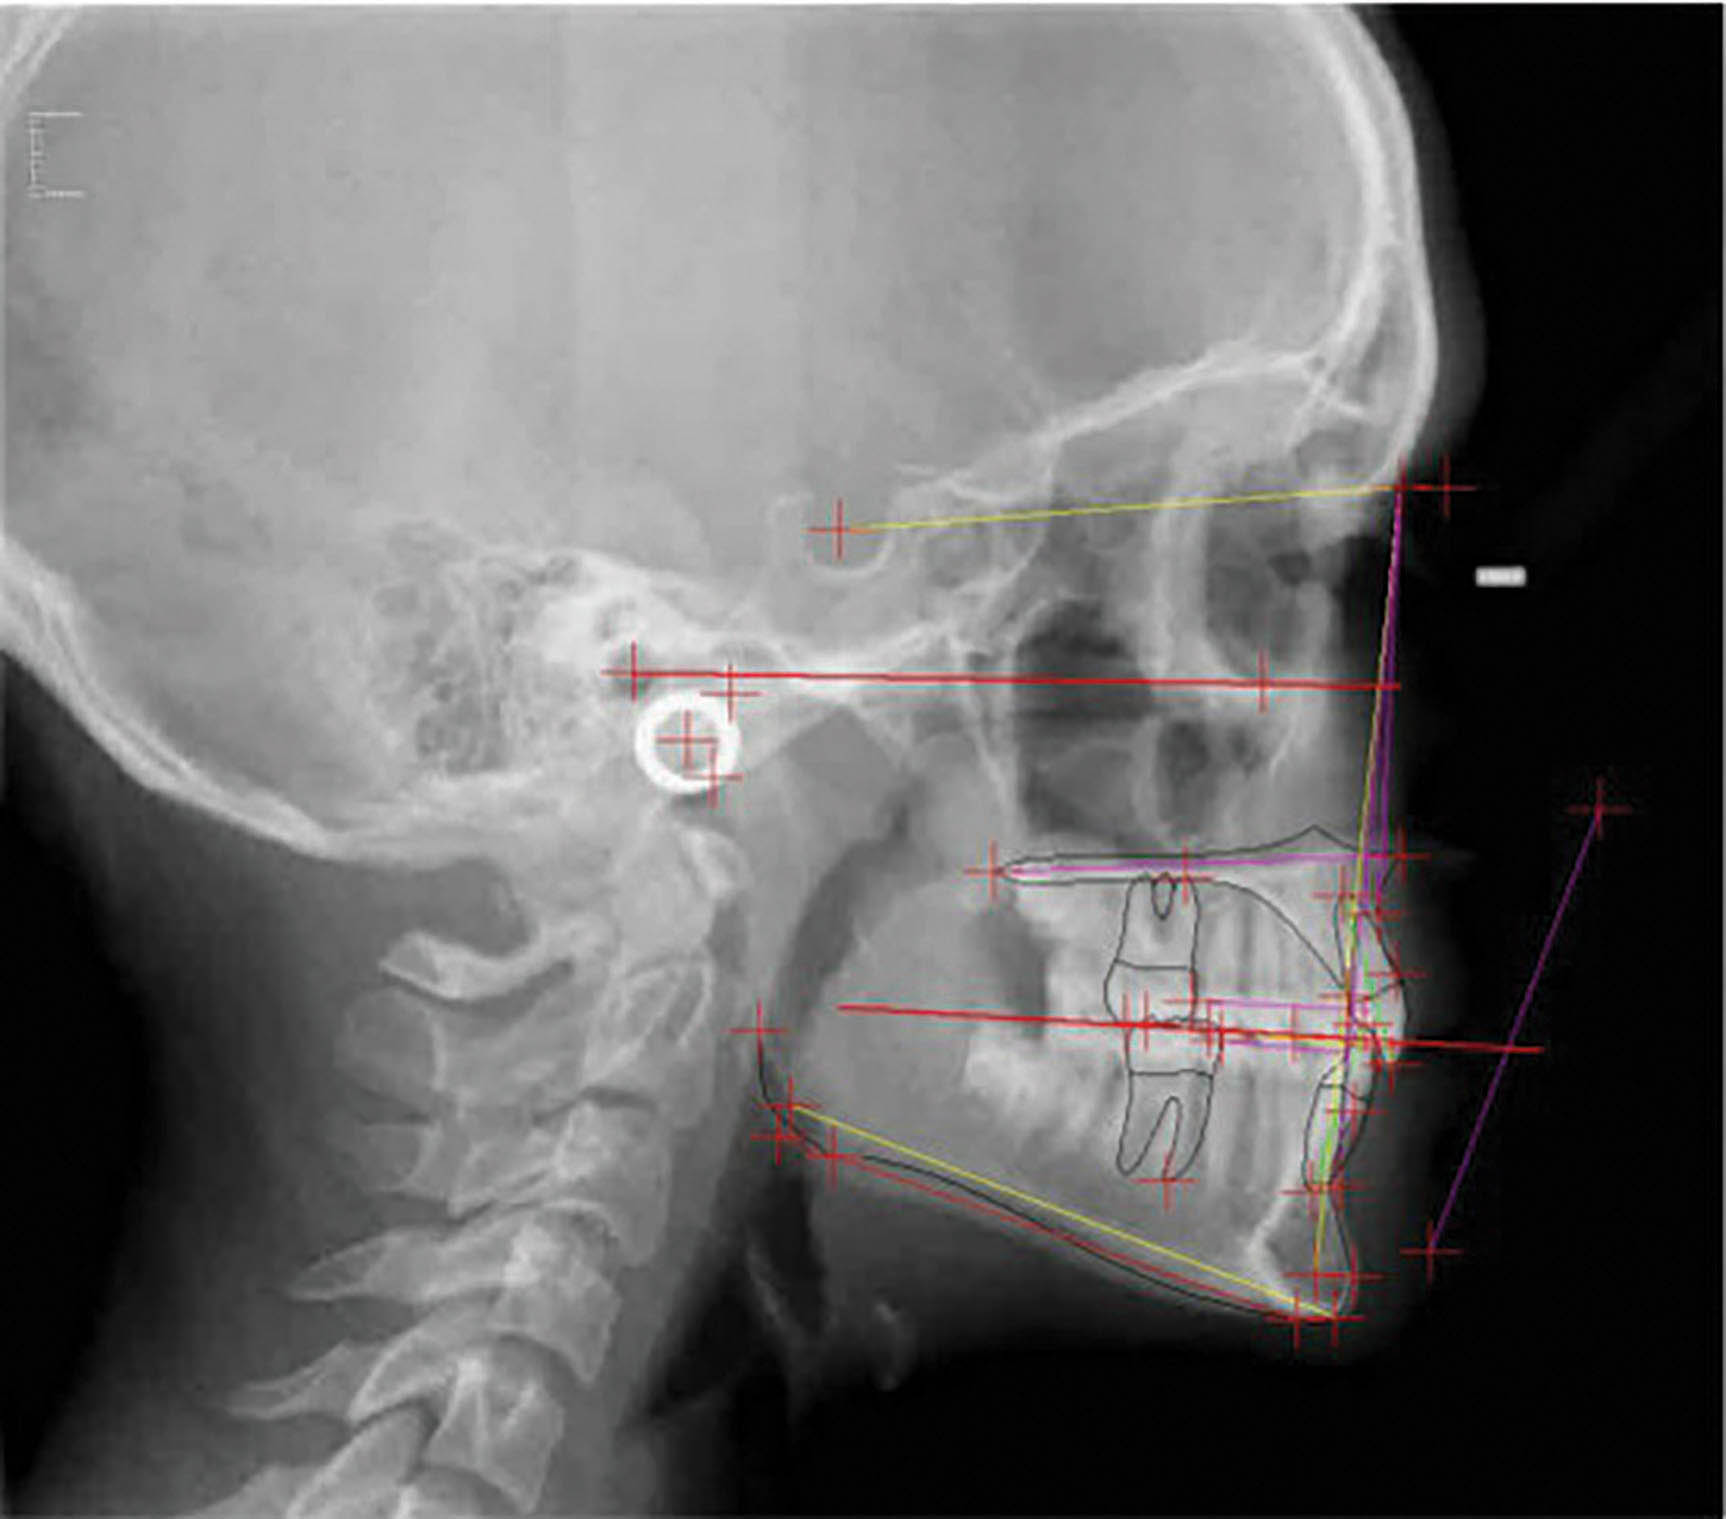

عکس OPG پایان کار (شکل 66-6) طبیعی است. سوپرایمپوز نمودن لترال سفالومتریها (شکل 67-6) پروترود شدن انسیزورهای پایین را نشان میدهد که هم برای رفع کرادینگ و هم برای اینترود نمودن نسبی قدامیها مفید بود.

درمان بیمار ۲۴ ماه به طول انجامید و یک قالب گیری مجدد نیز داش

شکل 67-6